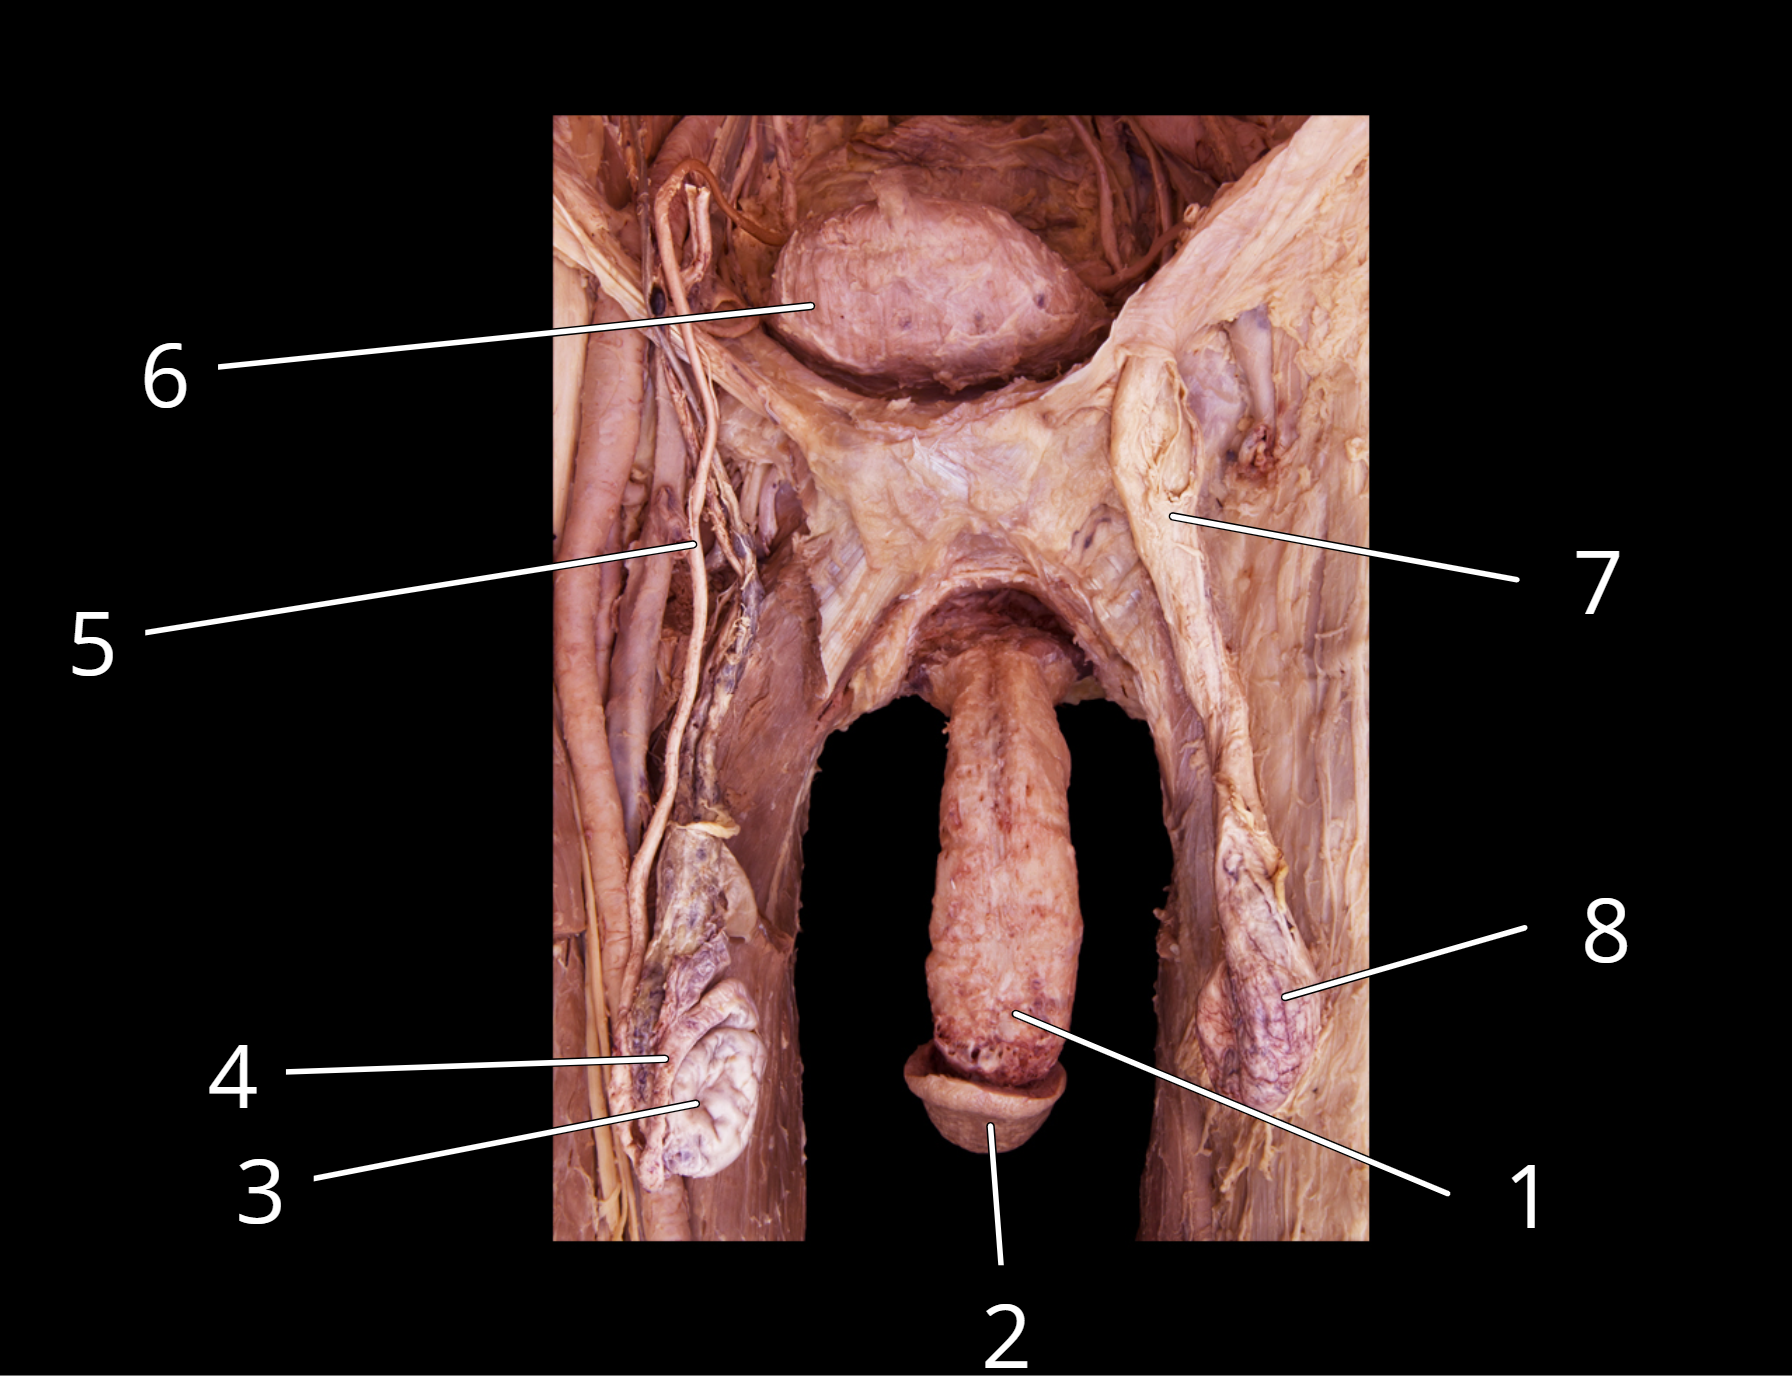

Male reproductive structures

1. Penis

2. Glans penis

3. Testis

4. Epididymis

5. Ductus deferens

6. Urinary bladder

7. Spermatic cord

8. Testis in external spermatic fascia